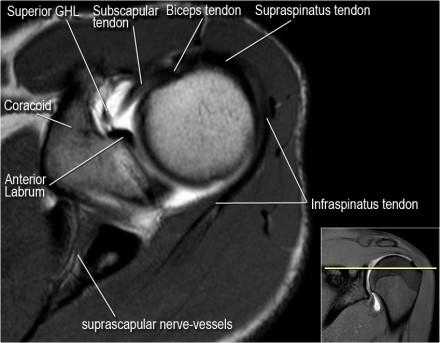

Изображение передних отделов плечевого сустава.

Сухожилие подлопаточной мышцы прикрепляется как к малому бугорку, так и к большому бугорку, давая поддержку длинной головке двуглавой мышцы в борозде двуглавой мышцы. Вывих длинной головки двуглавой мышцы плеча неизбежно приведет к разрыву части подлопаточной сухожилия. Манжета вращателей плеча состоит из сухожилий подлопаточной, надостной, подостная и малой круглой мышц.

Нормальная анатомия плечевого сустава в аксиальных изображениях и контрольный список.

- поищите os acromiale, акромиальную кость (добавочная кость, расположенная у акромиона)

- обратите внимание что ход сухожилия надостной мышцы параллелен оси мышцы (это не всегда так)

- обратите внимание что ход сухожилия длинной головки двуглавой мышцы в области прикрепления направлен на 12 часов. Область прикрепления может быть различной ширины.

- обратите внимание на верхние отделы суставной губы и прикрепление верхней плече-лопаточной связки. На данном уровне ищется SLAP-повреждение (Superior Labrum Anterior to Posterior) и варианты строения в виде отверстия под сутавной губой (sublabral foramen - подгубное отверстие). На этом же уровне по задне-боковой поверхности головки плечевой кости визуализируются повреждение Хилл-Сакса.

- волокна сухожилия подлопаточной мышцы, создавая бицепитальную борозду, удерживают сухожилие длинной головки двуглавой мышцы. Изучите хрящи.